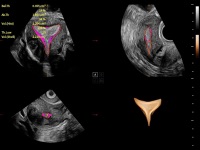

通过光照模型,使二维血流显示出立体的效果,增加血流的敏感性、成束性,减少外溢。可以和其他不同的血流技术联合使用,融合不同技术的优势。轻松应对微小血管,增强血流的立体效果,提升视觉敏感性。

通过创新的Matrix E自适应滤波算法,能有效滤除软组织和噪声信号,最大限度保留超低速微细血流的信号;结合超长时间域算法,极大提升细微血流的敏感性和空间分辨率,更真实的反应组织、包块的血流灌注情况。